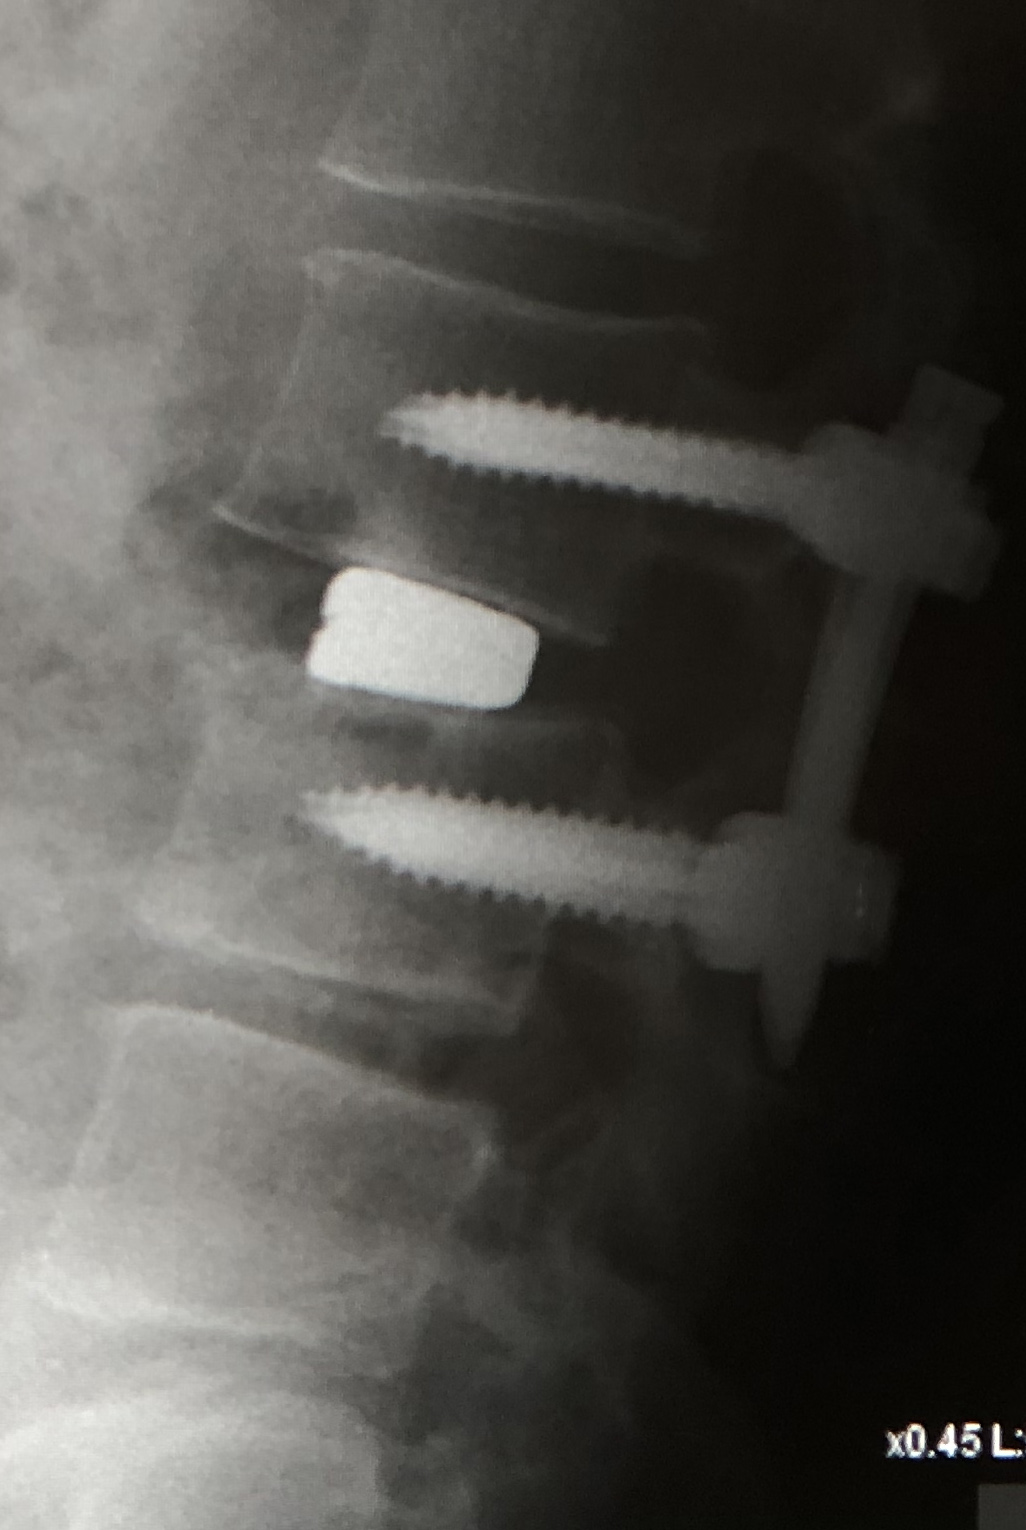

eXtreme Lateral Interbody Fusion(XLIF)は、主に左脇腹からの小皮切で腰椎に側方からアプローチし、脊椎前方に十分な骨移植を行ない脊椎の矯正固定を行なう手術方法です。脊柱管内には一切触れずにす椎間板の高さを増大させてすべりを矯正し、間接的な神経の除圧が可能です。

| 術前 | 術後 | |

|---|---|---|

| X線 |

|